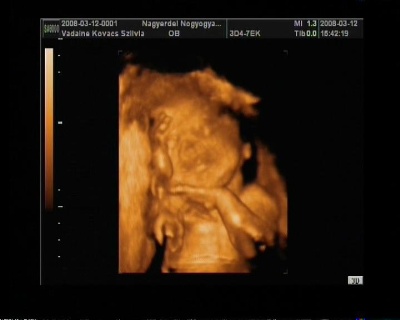

31 hetes

A doki szerint pufók kislány